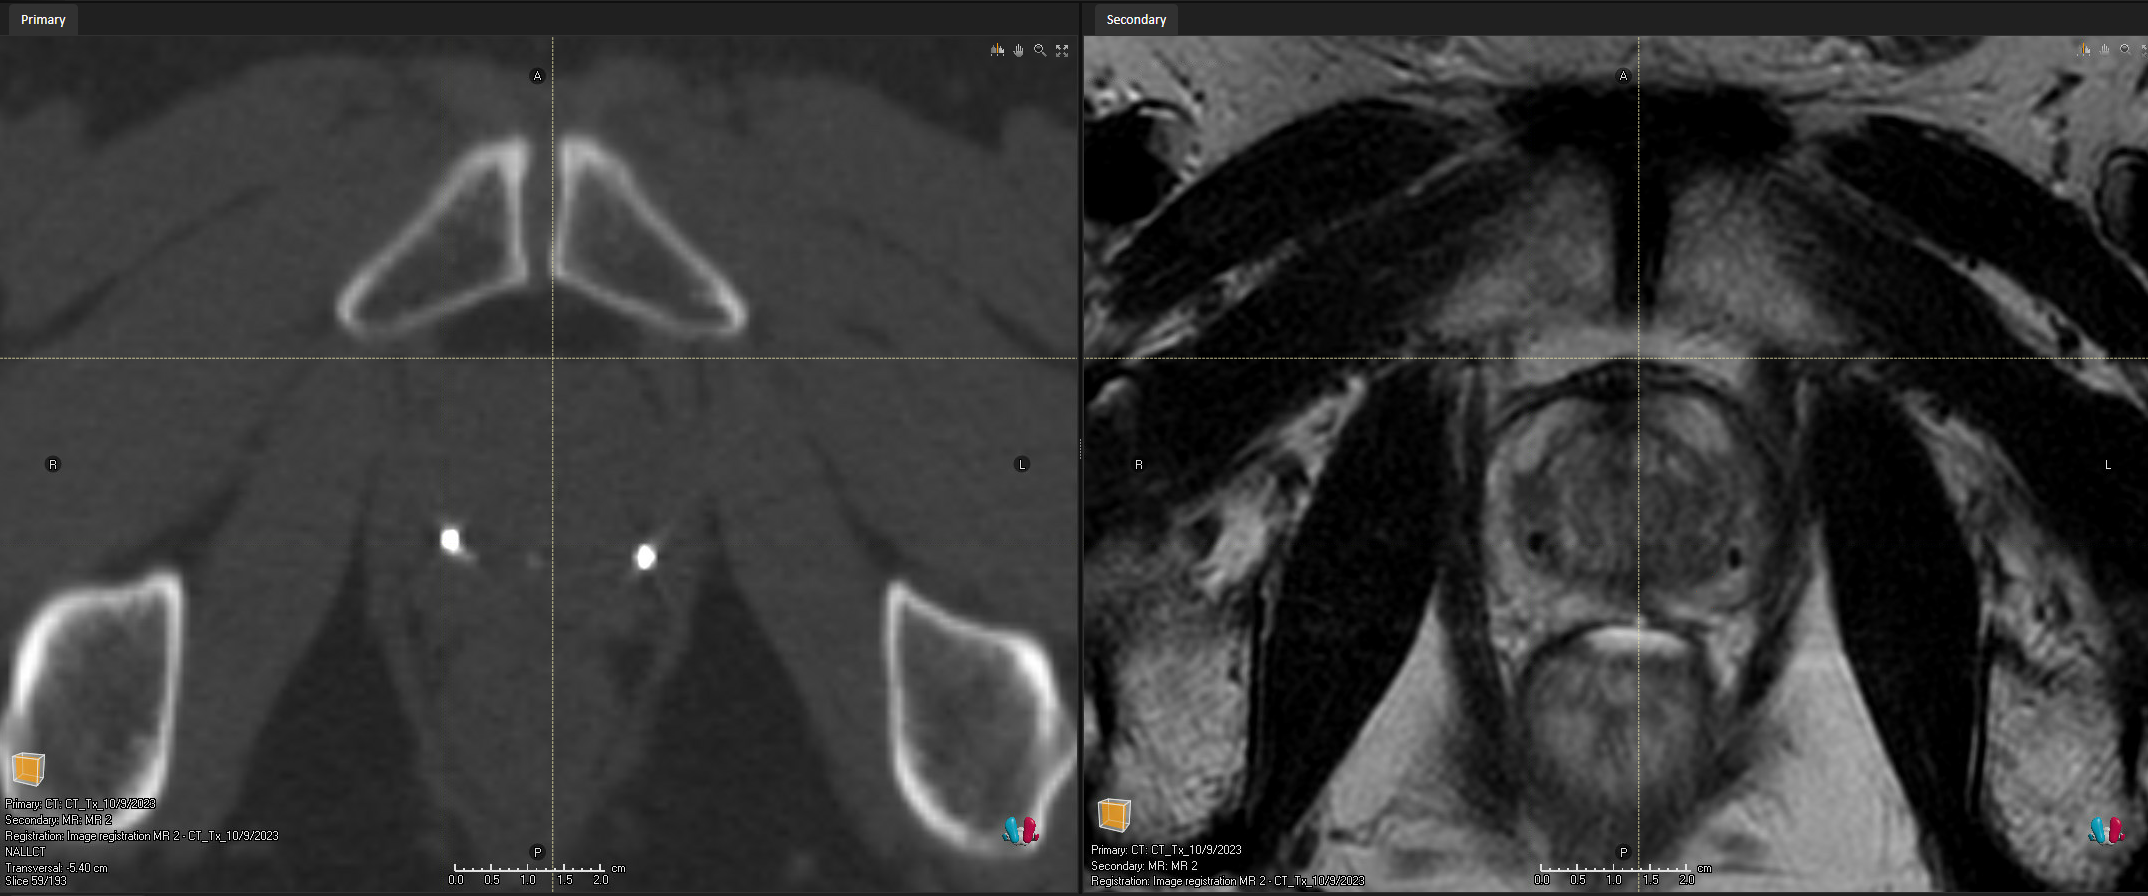

Easily register CT and MR images

Ball shaped Gold Anchor MR+ markers can typically be visualized directly on the T2-weighted MR sequences used for prostate delineation. This is very helpful when fusing CT and MR-images and may eliminate the need for an additional MR “marker sequence” and thereby enable a more precise fiducial-based image fusion. Read more here.

The MR+ marker material provides great MRI visibility, especially on T2-weighted images, which typically are used for prostate delineation. This helps when fusing CT and MR images and when moving to MR-only workflows.